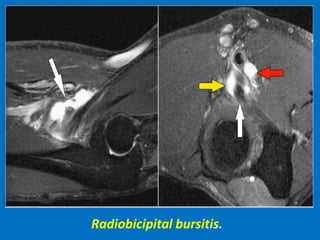

Radiobicipital bursitis.